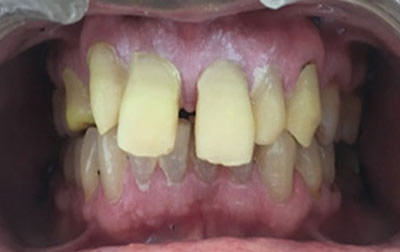

Zirconia Crowns:

For durable and aesthetically pleasing dental restorations, werecommend Zirconia Crowns, a type of tooth restoration treatment that covers severe decay and bad discoloration. Zirconia is a strong and biocompatible material that closely resembles the natural appearance of teeth. Our dental experts craft zirconia crowns with precision and artistry, ensuring a perfect fit and a seamless blend with your existing teeth. With zirconia crowns, you can achieve strong teeth and a pleasant smile.